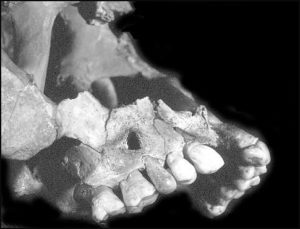

La prothèse dentaire ostéo-implantée montre à elle seule le caractère exceptionnel de ce crâne (fig.9).

En effet, la seconde prémolaire maxillaire droite a été remplacée par un pseudo-élément dentaire qui n’est ni une dent humaine, ni une dent animale, ni en ivoire, en bois mais en os. Elle est parfaitement immobile, sans aucune trace de collage.

Il s’agit d’un os de petite taille comme un os de la main, du pied ou d’une patte d’un petit mammifère dans lequel a été taillée, exécutée cette dent puis placée en bouche, mais impossible de savoir pour quelles raisons.

En vue vestibulaire ( fig.11a) le travail de l’artiste est étonnant tout comme l’idée de remplacer une dent par un autre matériau. L’os a été sculpté, caréné, galbé, rétréci pour figurer le collet et poli, ce qui lui donne vraiment l’aspect d’une couronne dentaire semblable à celles des dents voisines et ne se remarque pas d’emblée.

Sa face occlusale (fig.11b) est arrondie en massue et le diamètre vestibulo-lingual correspond à peu près à une demi dent. La phalange était donc trop étroite.

Sur la face palatine(fig.11c), le tissu spongieux de la phalange est visible grâce a une petite fracture du bord occluso-lingual. Cette pièce osseuse forme un solide assemblage avec l’alvéole, son ajustage est quasi parfait sur 3 faces. Toute la partie palatine de l’implant est dans le vide, ne comblant pas l’alvéole à cet endroit, si bien que l’on aperçoit parfaitement la pseudo-racine.

Le rebord alvéolaire, ne montre ni remaniement osseux, ni atrophie, ce qui laisse à penser que la restauration a été faite très peu de temps après la perte de la dent naturelle et très peu de temps avant la mort du sujet. Il existe un petit éclat alvéolaire vestibulaire qui a pu être fait lors de la pose de la dent avant ou après la mort du sujet.

Cet élément prothétique, mesure environ 20 mm de hauteur totale dont 8 sont à l’intérieur de l’alvéole, avec lequel il forme un assemblage solide, quasi-parfait. Nous avons là un os emboîté, fiché dedans l’os maxillaire et totalement immobile réalisant ainsi une » gomphose » selon les termes d’Ambroise Paré qui pensait, semble t-il, que les dents étaient articulées par gomphose (Littré, 1971).